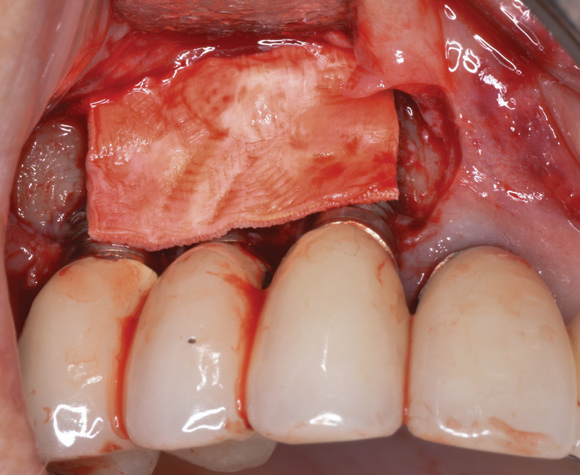

(8.) A cross-linked collagen scaffold consisting of FDBA/DBBM in a 4:1 ratio is placed over the particulate bone graft.

Figure 8

(10.) Primary, submerged closure is achieved over the newly placed implant and regenerative biomaterials.

Figure 10